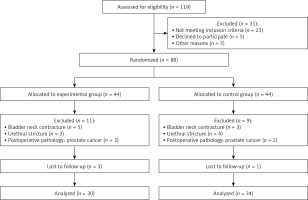

This study was conducted following the Declaration of Helsinki. The institutional Review Board of Hefei Second People’s Hospital approved the study. Informed consent was obtained by all subjects when they were enrolled. The inclusion criteria were: males 55–70 years old with normal ejaculation function, signed the approved informed consent, diagnosis of BPH based on clinical history, digital rectal examination, urinalysis, transrectal ultrasound, and prostate-specific antigen and TURP indicated. The exclusion criteria were: neurogenic bladder, history of prostate surgery, combined with bladder neck contracture, urethral stricture and other diseases that may cause bladder outlet obstruction, and postoperative pathological examination confirmed prostate cancer. The same surgeon performed all operations. BPH patients meeting the inclusion criteria were randomly divided into the Control group (traditional TURP) and the Experimental group (complete reserved ejaculatory duct) in a ratio of 1 : 1. Finally, a total of 64 BPH patients were included in the analysis, including 34 cases in the Control group and 30 cases in the Experimental group. Figure 1 summarizes the flow diagram.